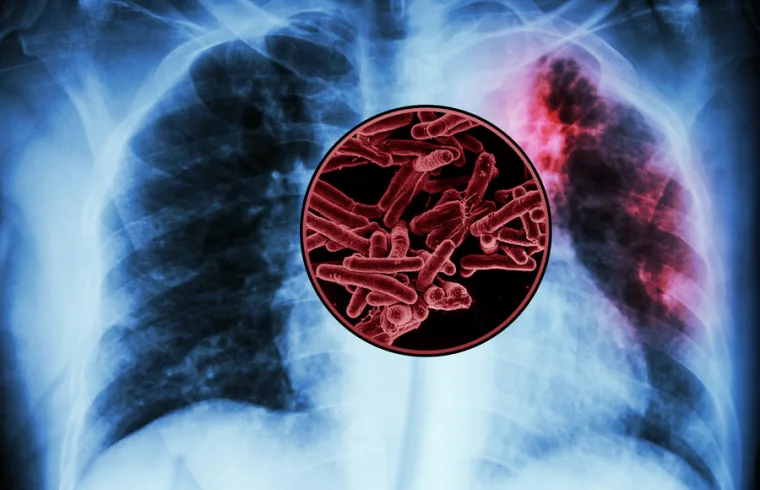

CAMBRIDGE, MA — A large-scale screen of tuberculosis proteins has revealed several possible antigens that could be developed as a new vaccine for TB, the world’s deadliest infectious disease.

There is currently only one vaccine for tuberculosis, known as BCG, which is a weakened version of a bacterium that causes TB in cows. This vaccine is widely administered in some parts of the world, but it poorly protects adults against pulmonary TB. Worldwide, tuberculosis kills more than 1 million people every year.

Since the BCG vaccine was developed more than 100 years ago, no other TB vaccines have been approved for use. Mycobacterium tuberculosis produces more than 4,000 proteins, which makes it a daunting challenge to pick out proteins that might elicit a strong immune response if used as a vaccine.